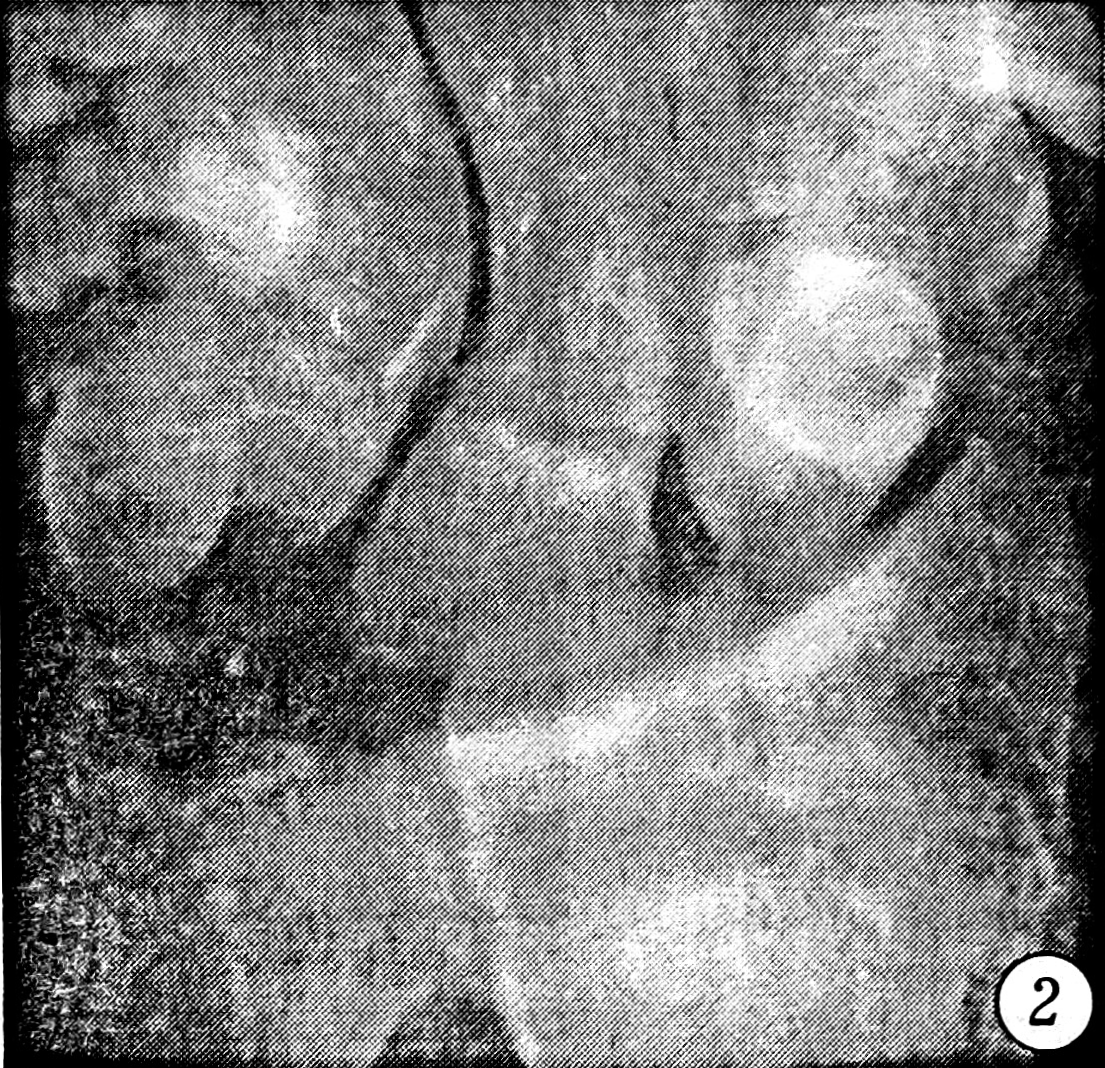

Исследовались первичные рентгенограммы и контрольные, сделанные после выполнения репозиции. Отбирались те случаи, в которых хотя бы на одном снимке присутствовали один или несколько из следующих рентгенологических признаков повреждения межзапястных связок: увеличение полулунно-ладьевидного угла более чем до 70° (рис. 1), симптом «кольца» дистального полюса ладьевидной кости (рис. 2), изменение формы и расширение полулунно-ладьевидного промежутка до 3 мм и более (рис. 3), нарушение непрерывности трех «запястных арок» (рис. 4), расширение полулунно-трехгранного промежутка (рис. 5) и увеличение полулунно-головчатого угла более чем до 20° (рис. 6) [5]. Результаты исследования представлены в табл. 1.

Рис. 2. Симптом «кольца» дистального полюса ладьевидной кости.